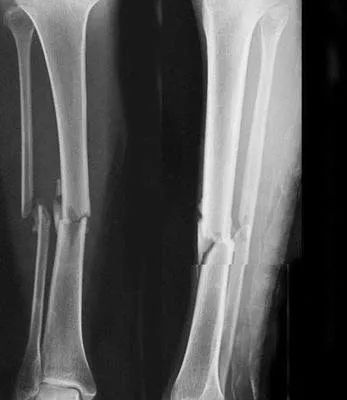

5、小腿踢球时骨折过,还能当兵吗?

四肢单纯性骨折,治愈1年后,X线片显示骨折线消失,复位良好, 无功能障碍及后遗症(空降兵除外),合格。6 、做过阑尾或疝气手术可以吗